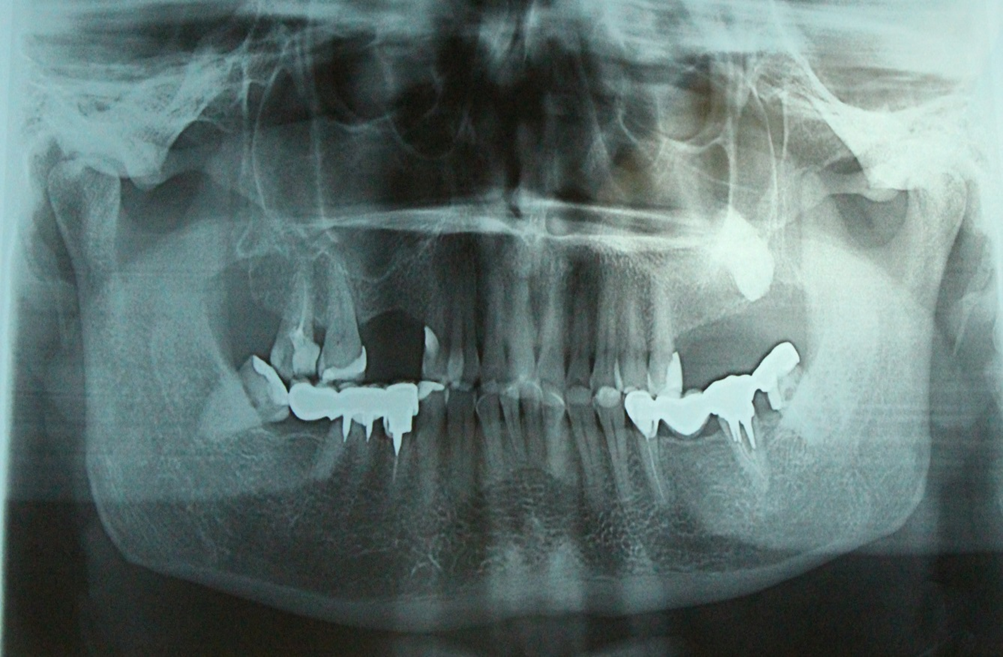

Клинический случай десквамативного глоссита на фоне гальваноза, участки десквамации визуализируются в области цельнолитых коронок с шероховатой окклюзионной поверхностью

Жжение постоянно, усиливается к вечеру. Пациенты часто связывают появление жжения после повторного ортопедического лечения или после 10–15 лет пользования металлическими протезами Рис.30.